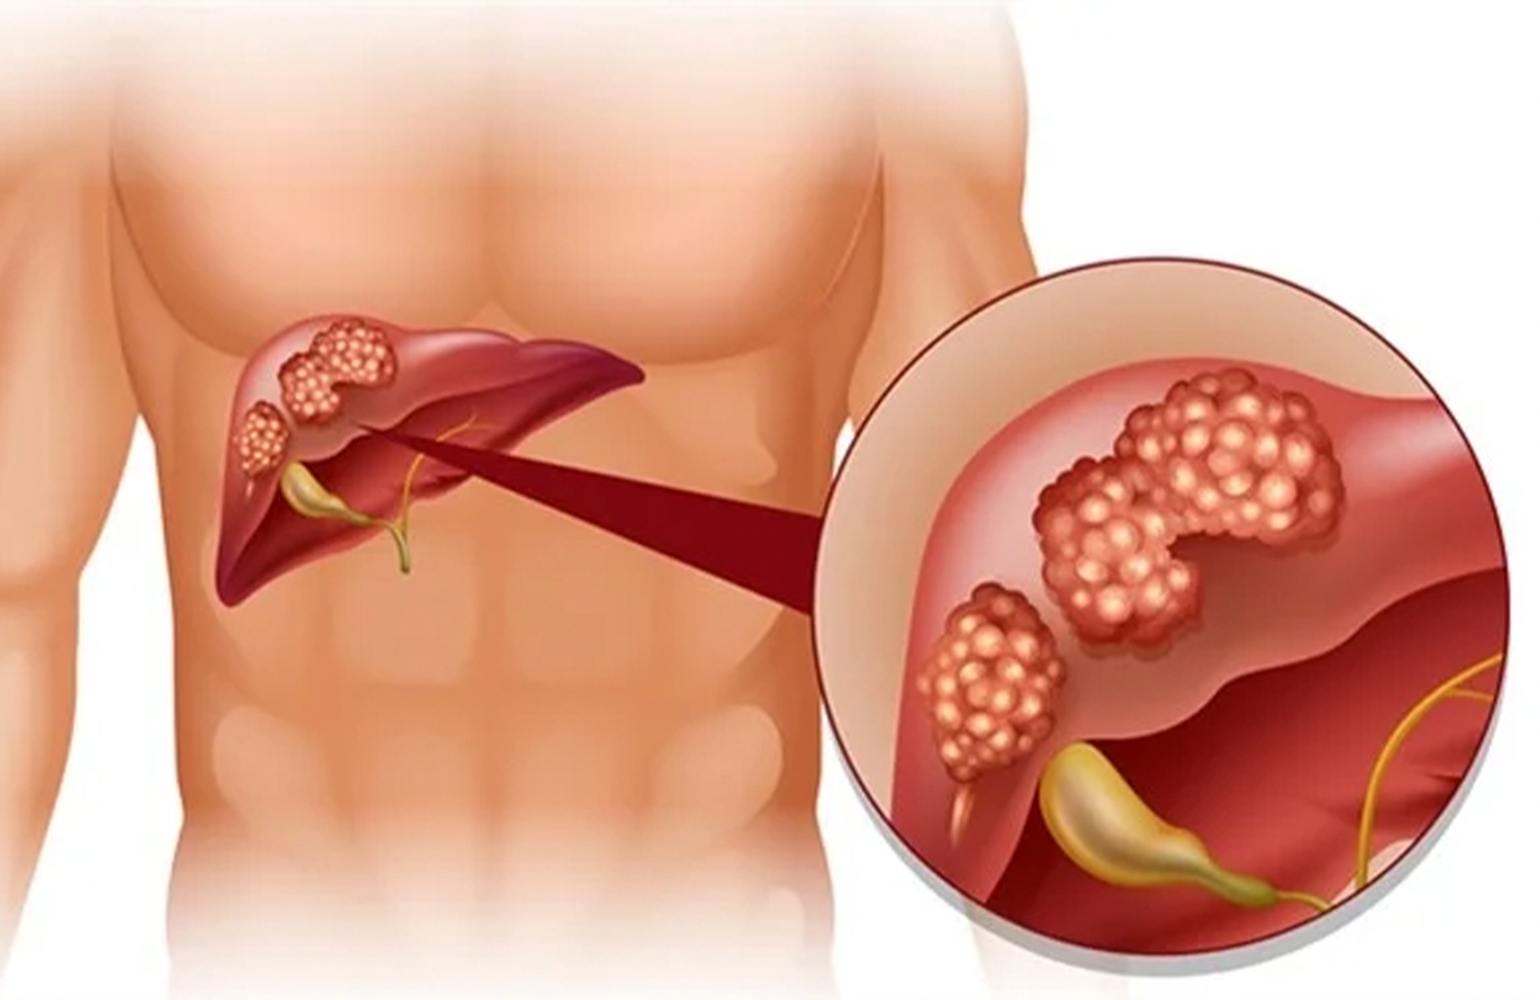

Detaylı BilgiKaraciğer Kanseri

Karaciğer kanserleri, karaciğerin kendi parankim dokusunda ortaya çıkan tümörler olarak tanımlanabilir.